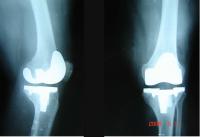

| 【文/陳堂麒】 有關節軟硬骨受損的民眾有福了!工研院與台大醫院歷經5年共同研發合作的「兩相軟硬骨關節修復技術」,有了重大的突破。 目前,這項研發已經在動物試驗上有了令人振奮的成果,預計將在今年7月,於台大醫院進行人體臨床試驗,預計最快3~5年後,便可以應用在臨床病患。 工研院生醫所所長留忠正表示,「兩相軟硬骨關節修復技術」研究計畫是由台大醫院醫師提出臨床需求與設計,工研院則針對醫師的需求結合在生醫材料上的成果,共同設計出符合臨床應用的軟硬骨關節修復平台技術。 這項研究計畫由台大骨科部主任江清泉醫師及工研院生醫所廖俊仁博士共同主持,江清泉醫師所領導的團隊利用在幹細胞和組織工程學的基礎,應用於軟骨再生的技術,5年內,已經有6篇相關的論文刊載於國際知名醫學期刊中,研發成果已臻全球頂尖的水準。 不需要體外培養軟骨細胞 只需進行一次手術 江清泉醫師表示,手術過程中,僅截取患部少量不受力處的健康軟骨切碎,浸泡於特殊酵素溶液中,讓軟骨細胞游離出來,載入上層軟骨、下層硬骨的兩相多孔載體中,植入患部後,軟硬骨短期內便可自行增生修復。 這項技術最大的特點是不需要體外培養軟骨細胞,患者只需要進行一次手術,便可以在最短的時間內,完成軟硬骨修復的工程,傷口小、復原快。 而且,目前全球的軟骨修復技術僅能修補軟骨缺損,而這項創新技術,則可以同時修復上方的軟骨組織及下方的硬骨組構。 廖俊仁博士指出,手術過程中只需擷取約2顆小米粒的軟骨細胞,再利用工研院研發出的軟骨迷你切碎機,將軟骨切碎成0.1公分大小,植入缺損處,軟骨細胞即可附著在載體上自行增生。 過去,治療關節炎與退化時,採用傳統軟骨移植必須經過兩次手術與麻醉,還需要在體外培養軟骨細胞,不但要符合相關規範與認證,且過程繁複、冗長,至少需耗時約3周,其中有2周的時間無法行動。 手術只需30分鐘 比傳統手術快上500~1000倍 而「軟硬骨關節修復技術」不需體外培養軟骨細胞,在手術台上即可擷取軟骨,病人僅需進行一次手術,手術只需30分鐘,比傳統手術快上500~1000倍,傷口極小,手術完畢後,幾乎可立刻下床。 適用範圍除了年輕人的運動傷害或外傷引起的關節軟骨缺損,更適用於中老年人小範圍的關節炎、關節退化和關節骨頭缺血性壞死。 江清泉醫師表示,目前研究團隊利用豬隻所做的動物實驗,大約半年骨頭可長全。在20隻豬的試驗中,整個手術採用關節鏡手術,傷口很小,實際過程只要30分鐘,三個月後,損傷處的軟骨復原良好。 未來可望適用於退化性關節炎、女性停經及老年關節出現病變,或是因為外力的造成的關節軟骨損傷。可為關節病變患者帶來創新、安全、有效的治療方法。 事實上,幾乎任何關節病變皆可使用,現在則會率先運用在膝蓋及髖關節處。不過,屬於類風濕性關節炎、痛風性關節炎的代謝性病變,則並不適用。 軟骨載體可被人體吸收 留忠正所長指出,為了順利推動該項產品的商品化,工研院特別開發方便醫師在手術台上便可以迅速處理的器具與載體:自體組織可拋棄式裝置、生物可吸收性骨材與微創手術器械,而這些都是在工研院生醫材料GMP工廠進行試量產。 相關產品技術,也在日前通過臨床前大型成熟豬隻動物試驗,對於修復深層關節軟硬骨損傷,有相當優異的表現。 廖俊仁博士表示,載體的材料類似手術縫線,含磷酸鈣成分,軟骨載體功成身退後可被人體吸收,硬骨載體會成為硬骨的一部分,預估未來的材料費在10萬元以內,若包含整個手術診療費用約需30萬元。 此一創新技術已接受專案輔導上市,目前正向衛生署申請臨床試驗,預計大約需要3~5年。 技術將移轉給美精技 拓展海外市場 為了加速「兩相軟硬骨關節修復技術」的研發與推廣,工研院與台大醫院亦正式將這項技術將移轉給全球知名的骨科醫材、關節產品領導廠商-美精技公司(Exactech)。美精技公司將同步展開全球性的臨床試驗,以完成包括:美國及歐盟等地區的上市作業。 這項技術完全由國人自行研發,除了極具指標意義之外,研發成果也申請7項專利(其中5項已通過)、完成動物試驗,同時,技術移轉給美精技公司。 希望藉由美精技公司在國際醫材市場豐富的產品開發經驗與市場行銷、通路,進行歐美市場的臨床試驗與商業化,未來將有助於國內骨科及醫療器材產業的發展。 美精技公司預計會先在美國進行人體試驗、在美國上市;該公司2007年營業額達1億2500萬美元,為全球第三大骨科醫材公司。 |